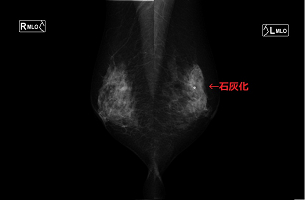

マンモグラフィとは乳がんを診断する方法の一つで、乳房専用のレントゲン撮影です。乳房はやわらかい組織でできているため、専用の装置を用います。触ってもわからないような早期の小さながんはもちろん、しこりを作らない乳がんを白い影や、非常に細かい石灰砂の影として見つけることができます。 撮影は、乳房を挟みながら圧迫して、上下方向から1枚、斜位方向から1枚ずつ計4枚撮影しますので、検査時間は約10分かかります。挟むことによる痛みには個人差がありますので、できる範囲で行います。これは乳房の内部をよりみやすくする為となるべく被曝線量を減らす為など理由があってのことなので、ご協力をお願いします。 |